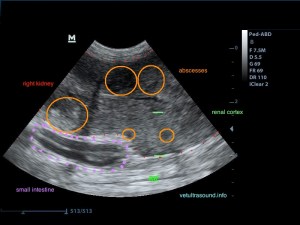

Ευρήματα: Στον υπέρηχο κοιλίας βρέθηκε επώδυνη διόγκωση και των δύο νεφρών με πάχυνση της φλοιώδους ουσίας, η οποία παρουσίαζε έντονη ανομοιογένεια. Οι νεφρικές πύελοι ήταν ήπια διατεταμένοι και στο εσωτερικό τους παρατηρήθηκε αφθονία ιζήματος. Οι ουρητήρες, οι οποίοι ήταν επίσης διατεταμένοι, απεικονίζονταν μέχρι την είσοδό τους στην ουροδόχο κύστη. Αφθονία ιζήματος βρέθηκε στην ουροδόχο κύστη. Η εικόνα αυτή είναι συμβατή με διάμεση νεφρίτιδα και στην συγκεκριμένη περίπτωση με πυοκοκκιωματώδη φλεγμονή των νεφρών, συνεκτιμώντας τα εργαστηριακά ευρήματα, τον έντονο πόνο και τη διάταση των ουρητήρων. Το resistive index ( δείκτης αγγειακής αντίστασης) βρέθηκε αυξημένο (0.77) σε μεσολόβιο αρτηρίδιο του νεφρού. Φυσιολογικά θα έπρεπε να είναι (0.6±0.06). Αυτό δείχνει πως το οίδημα του νεφρικού παρεγχύματος εξαιτίας φλεγμονής ή οποιαδήποτε άλλης διήθησης, νεοπλασματικής ή μη, πιέζει τα αγγεία και αυξάνει την αντίσταση του αίματος προς το νεφρό. Ένα επιπλέον διαγνωστικό βήμα για την διερεύνηση της αιτίας, για την αποτελεσματικότερη θεραπεία και την εγκυρότερη πρόγνωση, είναι η λήψη κυτταρολογικού υλικού από το νεφρικό παρέγχυμα και ούρου από τη νεφρική πύελο για καλλιέργεια, στα οποία ο ιδιοκτήτης δεν θέλησε να προχωρήσει.